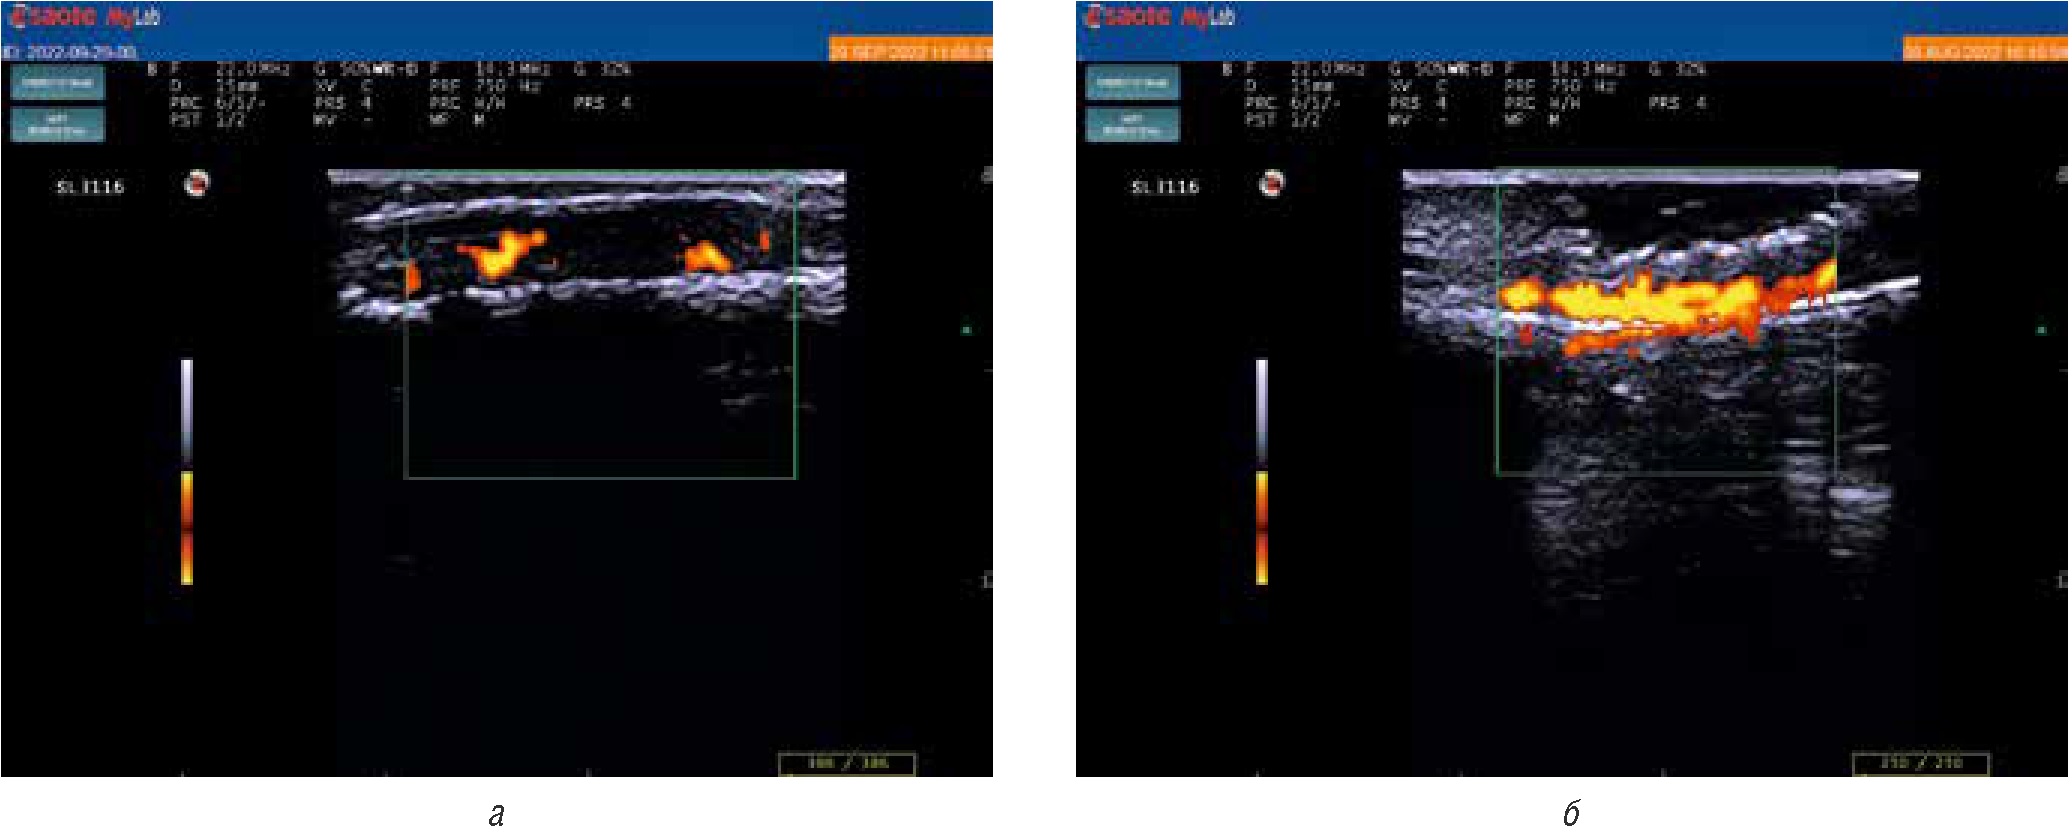

При оценке данных допплерографии ногтевого ложа у больных с псориатическим поражением ногтей (n = 34) признаки повышения кровотока 1-й степени наблюдались у 12 (35,3%) больных, 2-й — у 18 (52,9%), 3-й — у 4 (11,8%) (рис. 4). Среднее значение степени повышения кровотока составило 1,76. При сравнении суммарных значений индекса NAPSI в зависимости от степени повышения допплеровского кровотока отличий в его значениях между больными с 1-й степенью повышения кровотока (21,1 [14, 2; 28, 5]) и 2-й степенью повышения кровотока (22,1 [14, 5; 33, 7]) не наблюдалось (р = 0,15). Между тем при сравнении значений индекса NAPSI, полученных при клинической оценке одного ногтя (от 0 до 8 баллов) с наиболее высоким уровнем допплеровского кровотока, было отмечено, что для больных со 2-й степенью кровотока были характерны бо´льшие значения индекса (5,9 [3, 0; 6, 5]) по сравнению с больными с 1-й степенью повышения допплеровского кровотока (3,8 [2, 5; 4, 5]).

Рис. 4. Ультрасонография с допплеровским исследованием артериальных сосудов ногтевого ложа: а — несколько сливающихся допплеровских сигналов, соответствующих второй степени повышения кровотока; б — множественные сливающиеся допплеровские сигналы, соответствующие третьей степени повышения кровотока

Fig. 4. Doppler ultrasonography of arterial vessels in the nail bed; а — several confluent Doppler signals corresponding to the second degree of increased blood flow; б — multiple confluent Doppler signals corresponding to the third degree of increased blood flow

У 32 из 34 обследованных больных, имеющих признаки поражения ногтей, удалось провести спектральное допплеровское исследование артериальных сосудов ногтевого ложа в сравнении с характеристиками кровотока в здоровых ногтях (рис. 4). Количественные параметры допплеровского кровотока сосудов ногтевого ложа представлены в табл. 1.